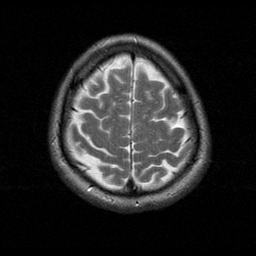

MR Study #1 -- Slice #20

[Home][Help][Clinical][Tour 1] Slice 20